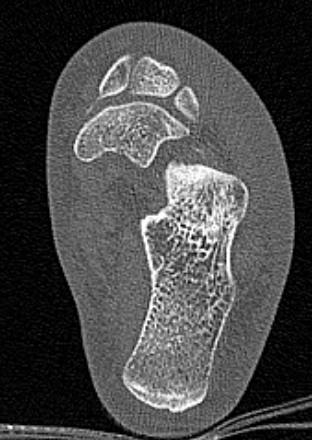

Во время исследования рентгеновская трубка томографа вращается вокруг исследуемой области и производит множество послойных снимков с шагом от 0,5 мм. Полученные снимки поперечного сечения с помощью компьютерной программы могут быть преобразованы в 3D-изображения исследуемого органа. Это позволяет выявлять различные патологические процессы на начальных стадиях и назначать своевременное лечение.

За счет быстроты, доступности и неинвазивности (то есть исследование не требует вмешательства в организм) метод КТ особенно востребован в ортопедии и травматологии. Мультиспиральная КТ лучше всего визуализирует плотные ткани, такие как кости и хрящи. Поэтому, в первую очередь, применяется для диагностики травм суставов (вывихов, подвывихов, переломов).

В отличие от обычного рентгена, при котором изображения костных структур накладываются друг на друга, что затрудняет диагностику, компьютерная томография дает возможность увидеть объемную модель сустава, наглядно оценить пространственное соотношение внутрисуставных структур, суставных поверхностей, расположение костных отломков при переломах и травмах. Это особенно важно в ходе подготовки к оперативному вмешательству и в послеоперационном периоде для оценки успешности проведенной операции.